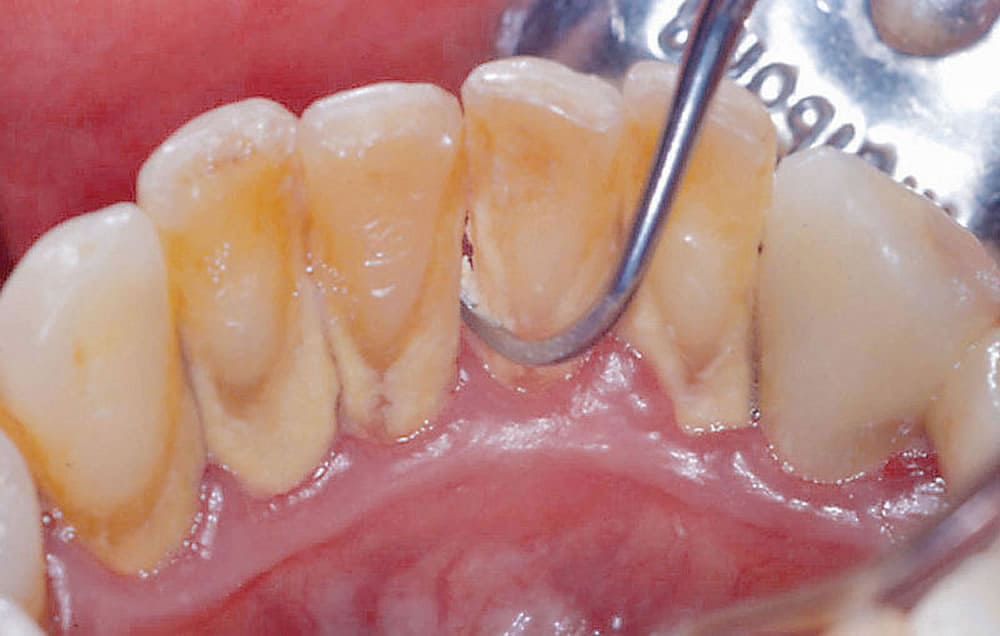

拡大視野による精密な歯石除去

歯周病の改善には、歯垢・歯石を取り除き、口腔内を衛生的に保つことが重要となります。鶴見あさがお歯科では、肉眼の8倍に視野を拡大できる歯科拡大鏡を駆使し、精度にこだわった歯石除去を実施しております。

視野を拡大することにより、歯周ポケット内の状態を目で確認することができるため、より精密な処置が可能となります。